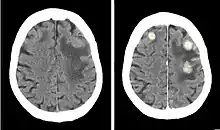

Iodinated contrast is a form of water-soluble, intravenous radiocontrast agent containing iodine, which enhances the visibility of vascular structures and organs during radiographic procedures. Some pathologies, such as cancer, have particularly improved visibility with iodinated contrast.

The radiodensity of iodinated contrast is 25–30 Hounsfield units (HU) per milligram of iodine per milliliter at a tube voltage of 100–120 kVp.[1]